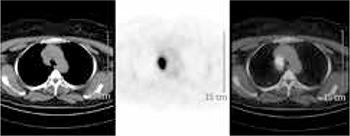

Positron Emission Tomography with 2-deoxy-[F-18]-fluoro-D-glucose (FDG-PET) has become a reliable diagnostic tool in clinical practice similar to Magnetic Resonance (MR) imaging and Computed Tomography (CT). FDG-PET has especially been used to differentiate malignant from benign lesions, and for staging and follow- up malignant tumors. However, FDG-PET has some pitfalls in cancer screening and FDG tracer accumulates at sites of infection and inflammation. Bone tuberculosis may be confused with malignant tumors of bone and its metastases, and can accumulate focally increased FDG in active period. We present a 60-year-old woman with lytic bone lesions and mediastinal hypermetabolic foci, initially suspected to be malignant by means of FDG-PET and the other imaging modalities; however, bone biopsy confirmed the diagnosis of bone tuberculosis.

正电子发射断层扫描术结合2-脱氧-[F-18]-氟-D-葡萄糖(FDG-PET)已成为临床实践中一种可靠的诊断工具,类似于磁共振(MR)成像和计算机断层扫描(CT)。FDG-PET尤其用于鉴别恶性病变与良性病变,以及对恶性肿瘤进行分期和随访。然而,FDG-PET在癌症筛查中有一些缺陷,并且FDG示踪剂会在感染和炎症部位积聚。骨结核可能会与骨恶性肿瘤及其转移灶相混淆,并且在活动期可局部积聚增加的FDG。我们报告一名60岁女性,有溶骨性骨病变和纵隔高代谢灶,最初通过FDG-PET及其他成像方式怀疑为恶性;然而,骨活检确诊为骨结核。